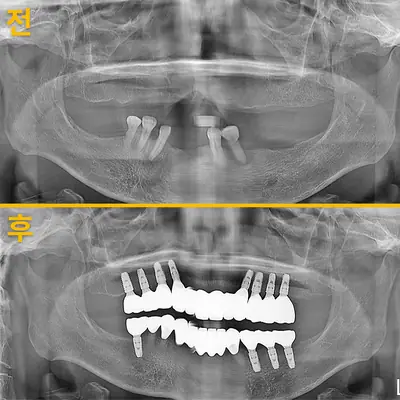

치과 치료를 두려워하는 분들을 위해, 진정요법을 활용한 사례를 소개합니다. 부산에 거주하던 60대 여성 환자가 치아가 많이 손상되어 임플란트와 브릿지 치료를 받았는데, 병원 트라우마와 공포로 어려움이 있었어요. 의식하 진정요법을 통해 깊은 낮잠 같은 상태에서 안전하게 치료를 받았고, 수술 과정도 성공적이었어요. 이 방법은 전신마취보다 안전하고, 환자도 큰 두려움 없이 치료를 마칠 수 있어요. 치과 공포증이 심한 분들도 전문가와 상담 후 진정요법을 고려해보시면 좋겠습니다.